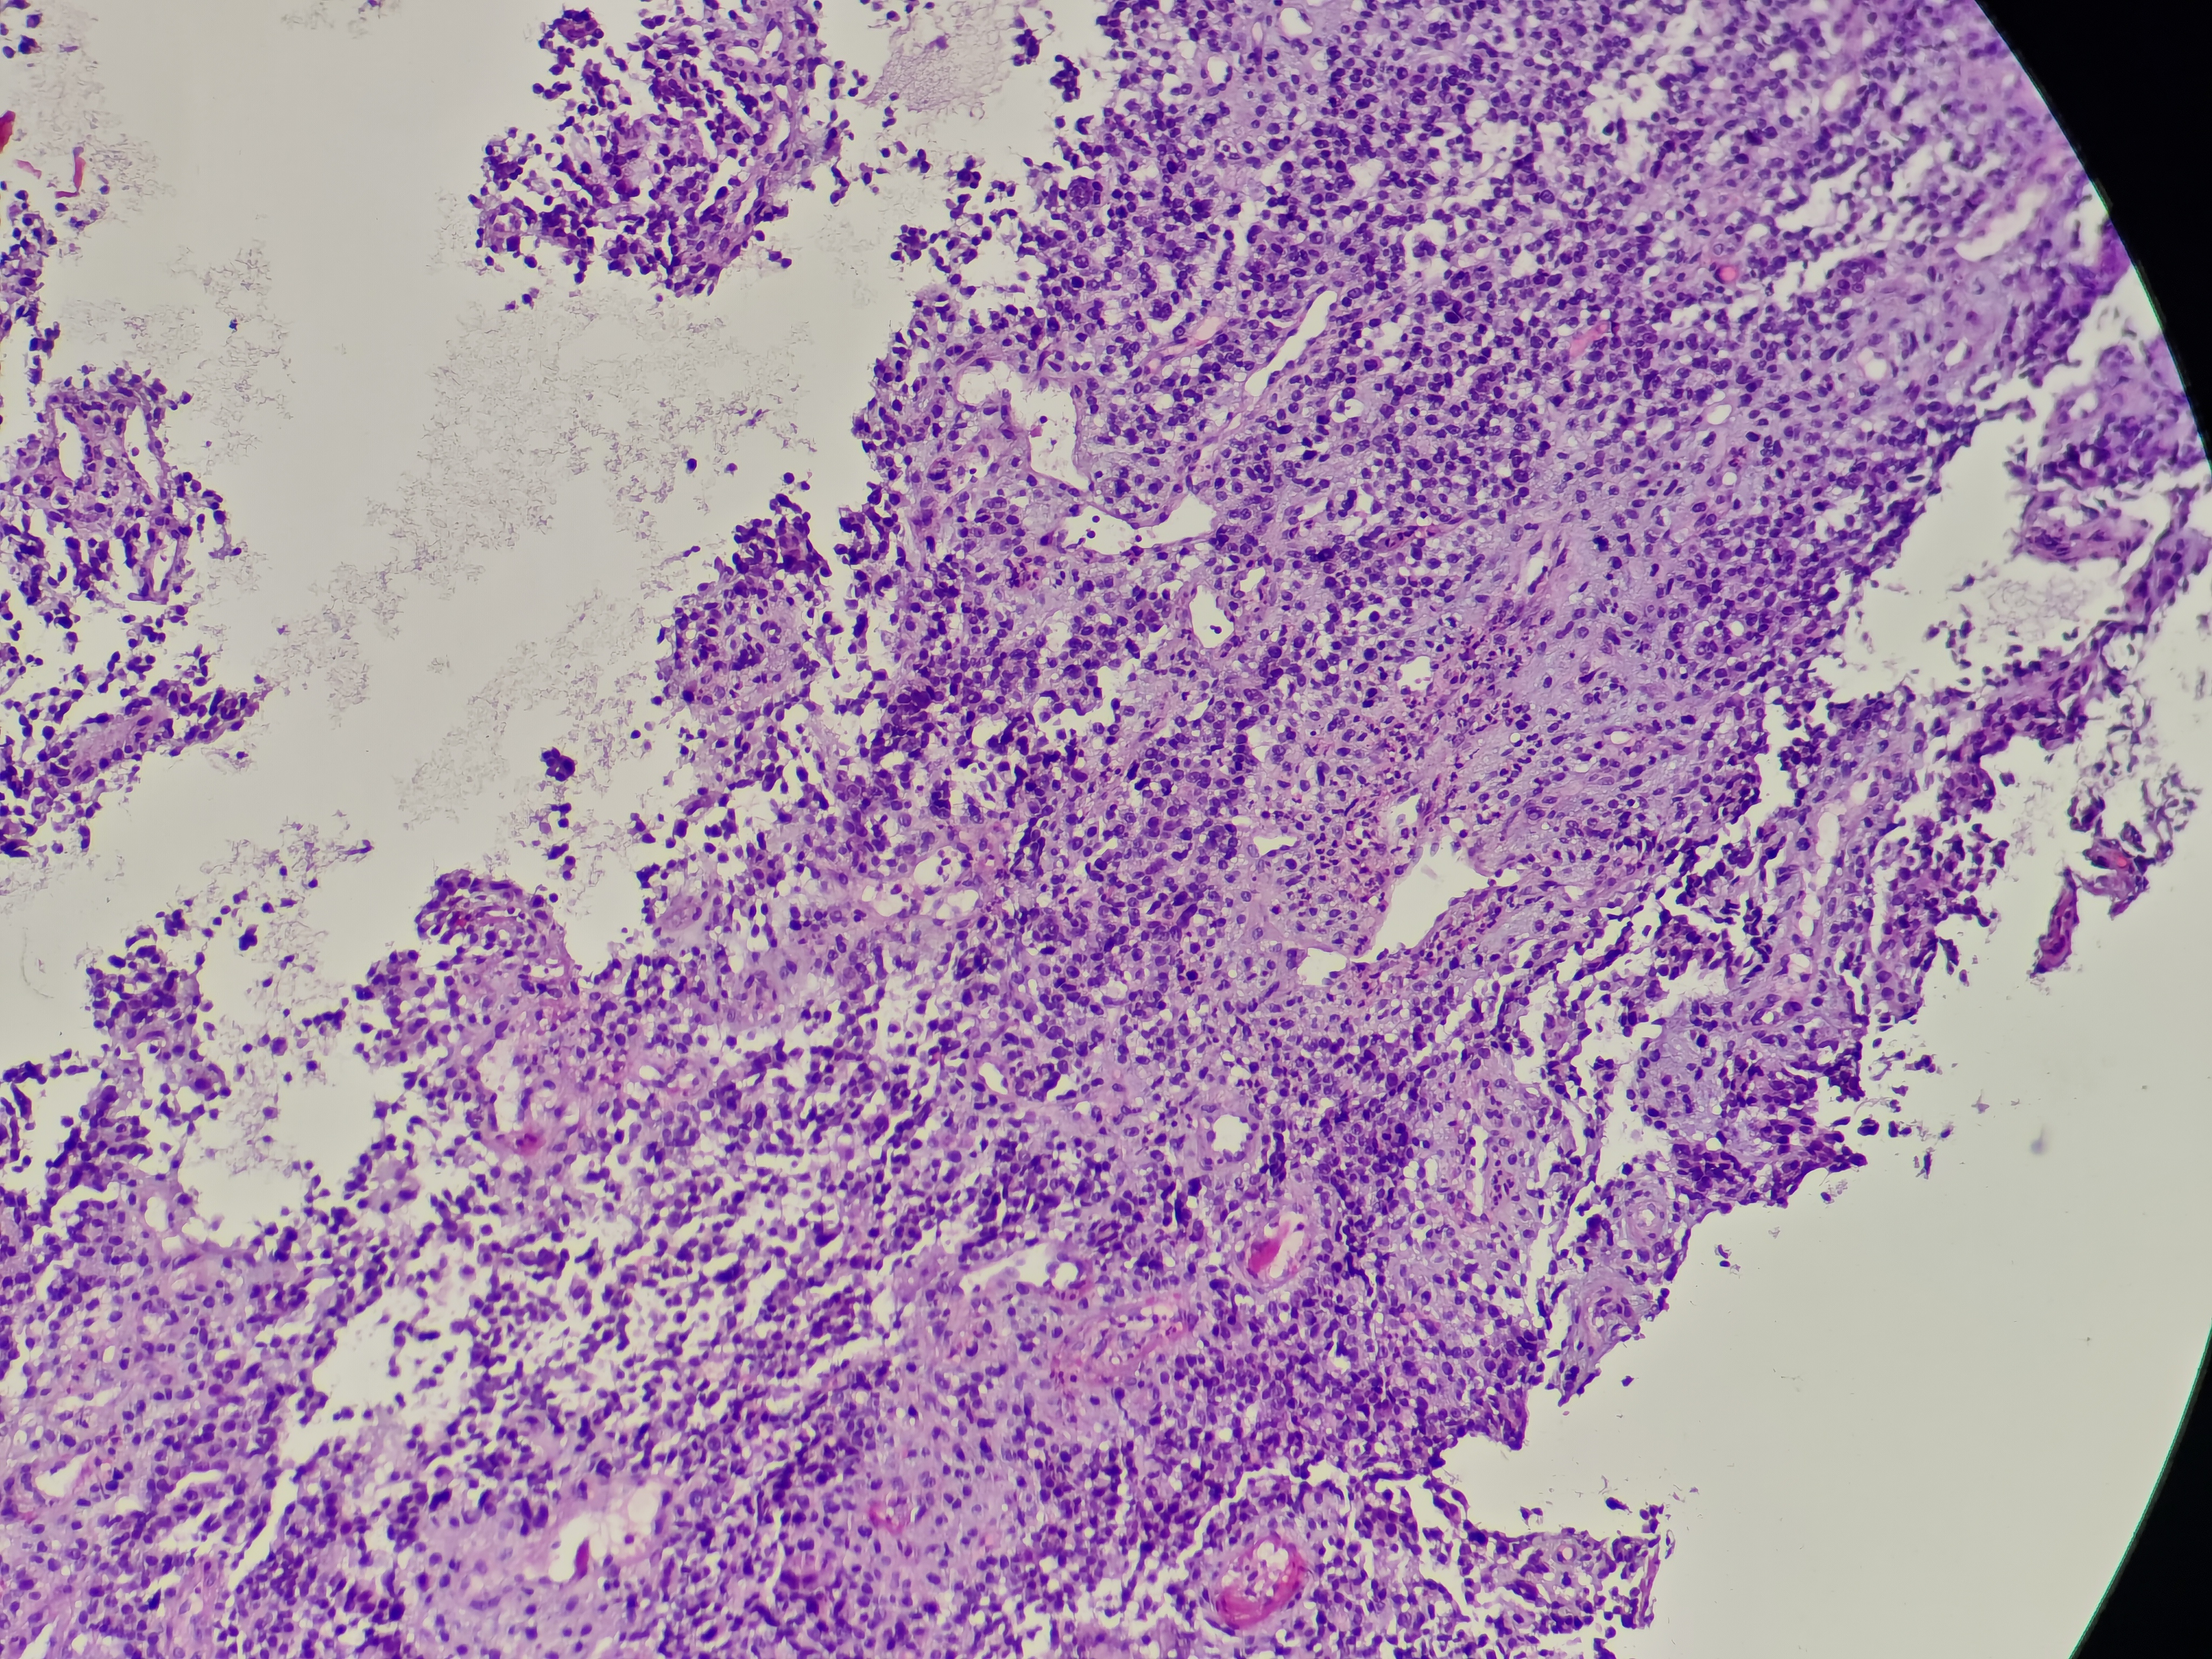

食管癌

食管距门齿33~38cm处可见环管腔半周隆起性病变,表面破溃,易出血,活检6块,质脆

食管活检

灰白软组织6块,直径0.1~0.2cm

请教老师,这个报什么癌?

图3